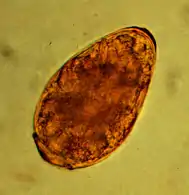

Infection with the kidney worm dioctophyma renale is only found in southern Europe, Asia and North America and is also rare in cats there, the main host being mink. The kidney worm is the largest parasitic nematode with a length of up to one meter and shows a twofold host change: first intermediate hosts are Oligochaeta, second freshwater fish. In the final host it parasitizes mainly in the renal pelvis or fat. Infestation of one kidney usually proceeds without signs of disease. If both kidneys are affected, renal dysfunction may occur as a result of hydronephrosis or pyelonephritis. The infection can be detected by kidney biopsy or imaging techniques. The barrel-shaped, yellow-brown, and 71-84 × 45-52 µm² eggs only appear in urine sediment when a female and male kidney worm meet in one kidney.[9]